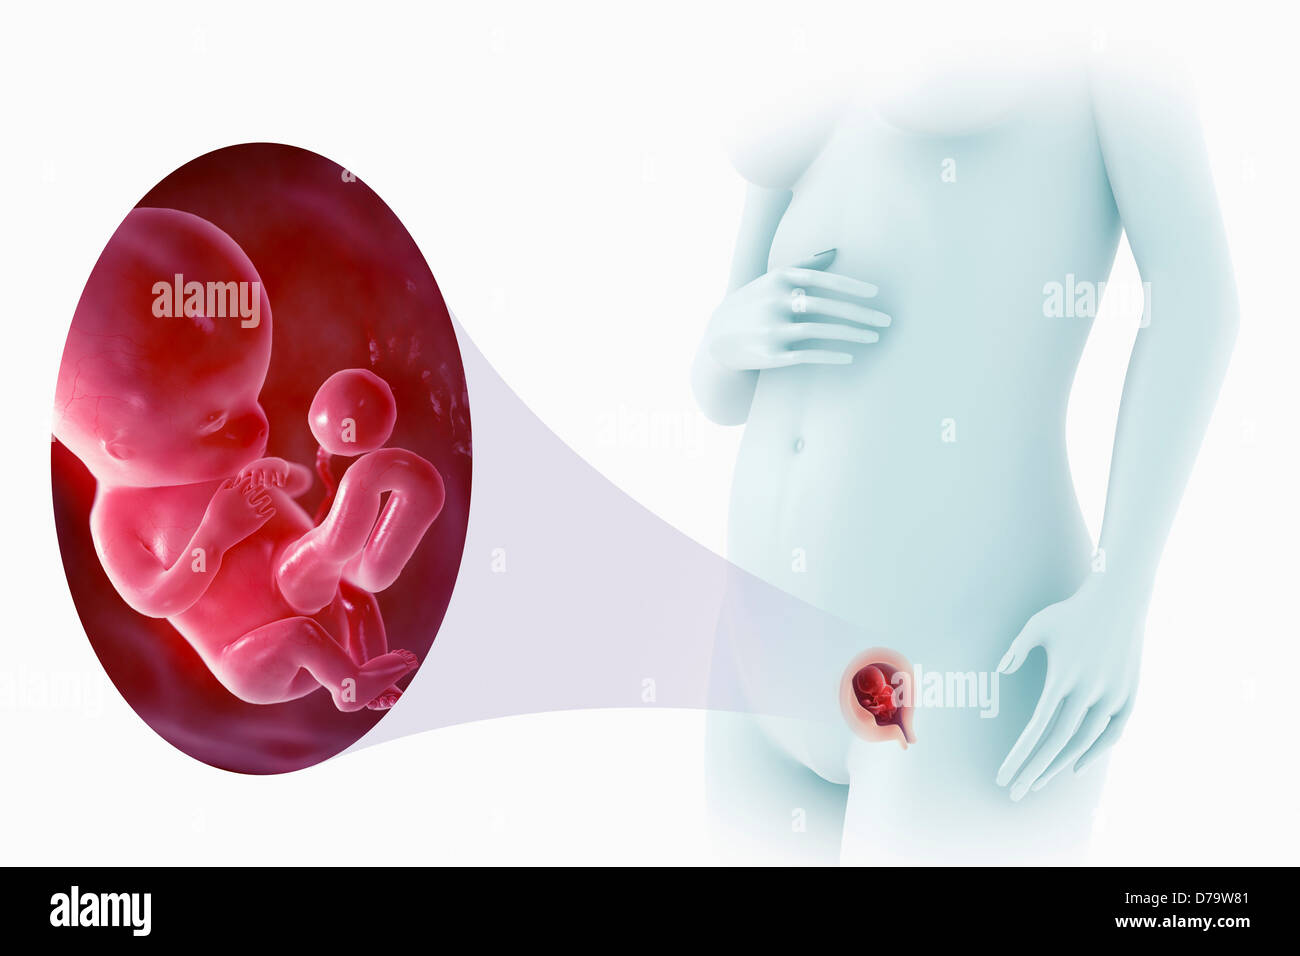

Ребёнок на 10 неделе беременности

Ребёнок на 10 неделе беременности

Ребёнок на 10 неделе беременности